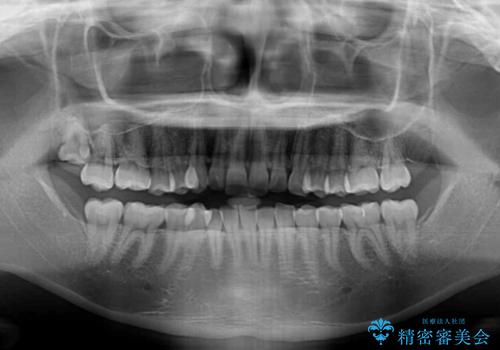

- 上下前歯のデコボコを気にして来院された患者様です。

下顎前歯が1歯欠損しているため、上下正中は合わず、左右奥歯の咬み合わせは理想的とはならない仕上がりとなります。